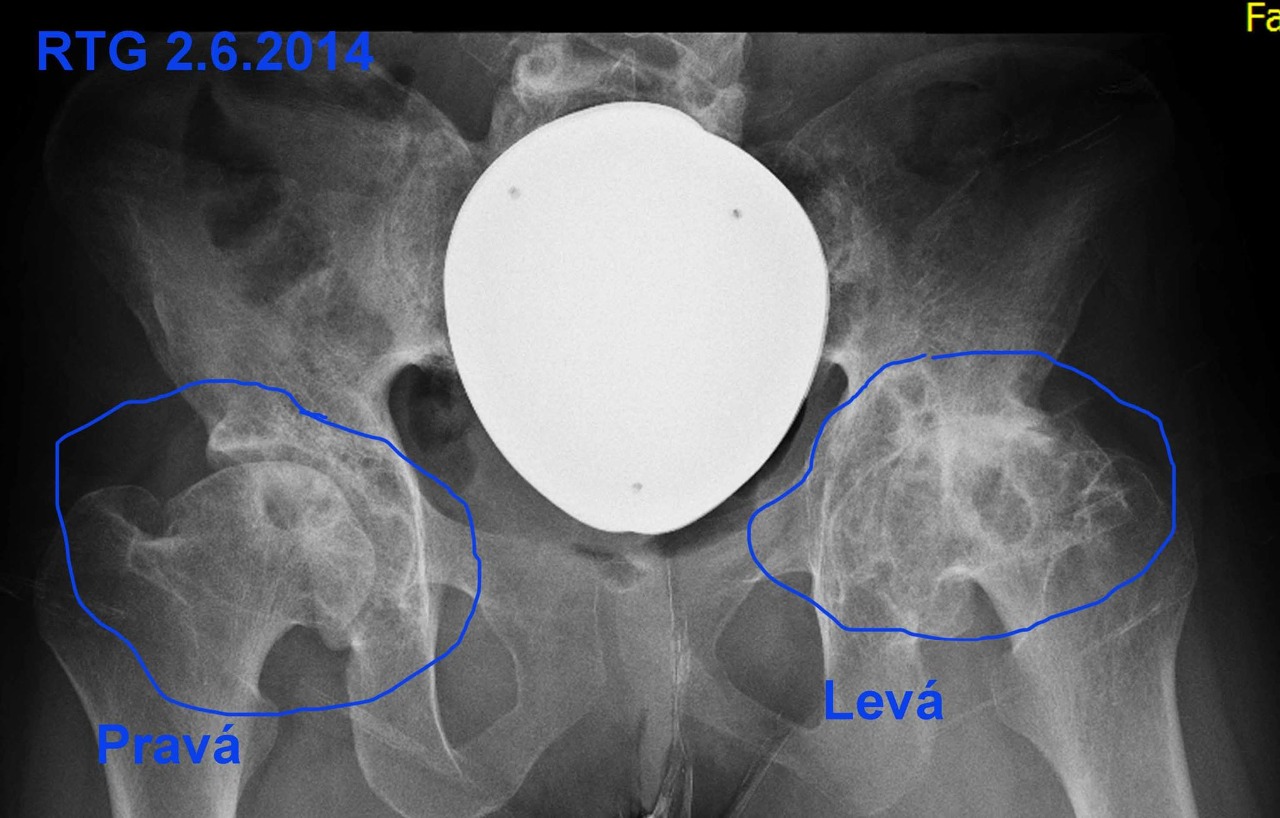

Následkem prodělané chemoterapii a radioterapii mám v současné době diagnostikovánu zejména artrózu IV. stupně v levé kyčli a koleni (nelze chirurgicky řešit), III. stupně v pravém koleni, kyčli a II. stupně v obou kotnících. Současně mi bohužel diagnostikovali silnou osteoporozu.